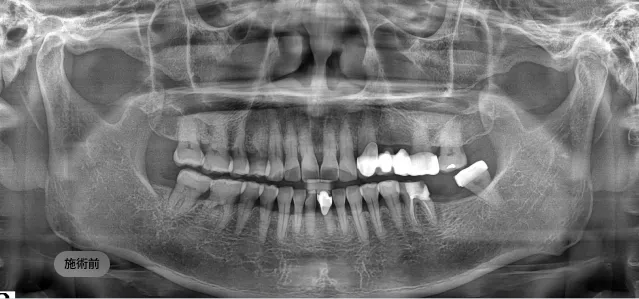

画面をドラッグして前/後を比較してみてください

3D CTと口腔スキャナーを用いて骨の状態を精密に分析し、患者様の健康状態を考慮した1:1オーダーメイド治療計画を立案します。

計画された位置に人工歯根(インプラント体)を正確に埋入します。必要に応じて、不足している骨を補う骨造成(骨移植)を同時に行います。

長く、健康に使えるインプラントのために ブランシュ歯科は施術より「設計」を先に考えます。

精密CT、3Dシミュレーションで 正確な骨の状態を分析します。

精密診断